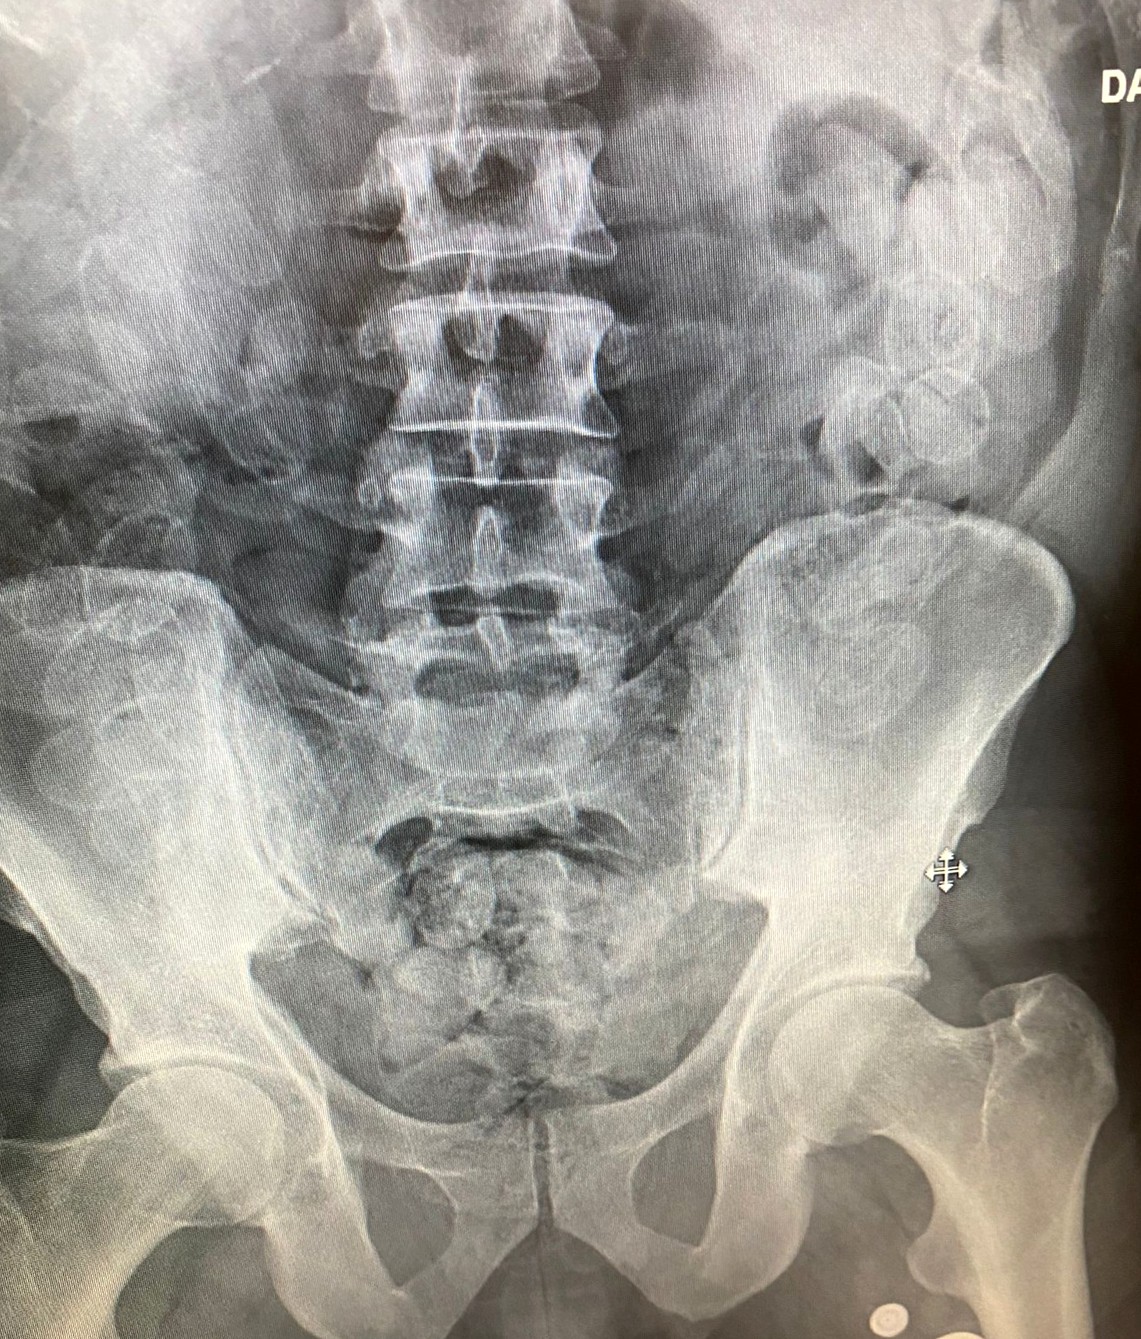

Antalya İl Emniyet Müdürlüğü Narkotik Suçlarla Mücadele Şube Müdürlüğü Hudut Kapıları Büro Amirliği tarafından il genelinde uyuşturucu maddelerin kaynağının kurutulması, ticaretinin ve kullanımının engellenmesi amacıyla Antalya Cumhuriyet Başsavcılığı koordinesinde yürütülen çalışmalar doğrultusunda düzenlenen operasyonda uyuşturucu madde ele geçirildi. Antalya Havalimanı'na gelen Fas uyruklu H.L.'nin şüpheli tavırlar sergilemesi üzerine Narkotik Suçlarla Mücadele Şube Müdürlüğü Hudut Kapıları Büro Amirliği ekiplerince yaptırılan iç beden muayenesinde 100 adet kapsül halinde daralı bin 100 gram macun esrar maddesi yakalandı. Gözaltına alınan şüpheli H.L. hakkında “Uyuşturucu veya Uyarıcı Madde Ticareti Yapma veya Sağlama” suçlarından işlem yapıldı.